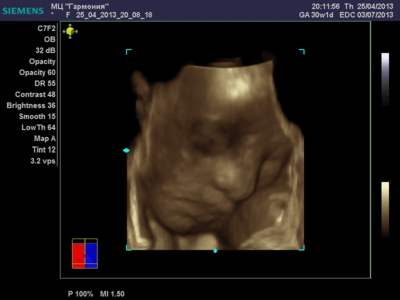

А я вчера на 3Д УЗИ ходила. Моя звезда закрывалась в еми 4мя конечностями. Просто пополам сложилась и спала себе сладко. УЗИстка провела со мной час, кое-как расшевелили маленькую, но ручка была постоянно на мордашке и засыпала она почти сразу снова. Я и на мяче прыгала и живот трясла. В конце более-менее фото вышли, но качество меня не порадовало. Возможно фри оф чардж еще раз переделают. Со средней фотки были отличного качества, а эти сплошное разочарование. Вот тут что-то более-менее еще. Главное пальчик оттопырила так смешно, мол минуточку. Вообще немного жутковатые фотки..хаха

image.jpg [ 47.86 КБ | Просмотров: 1458 ]

Еще одна, качество ужасное..

image.jpg [ 60.32 КБ | Просмотров: 1455 ]